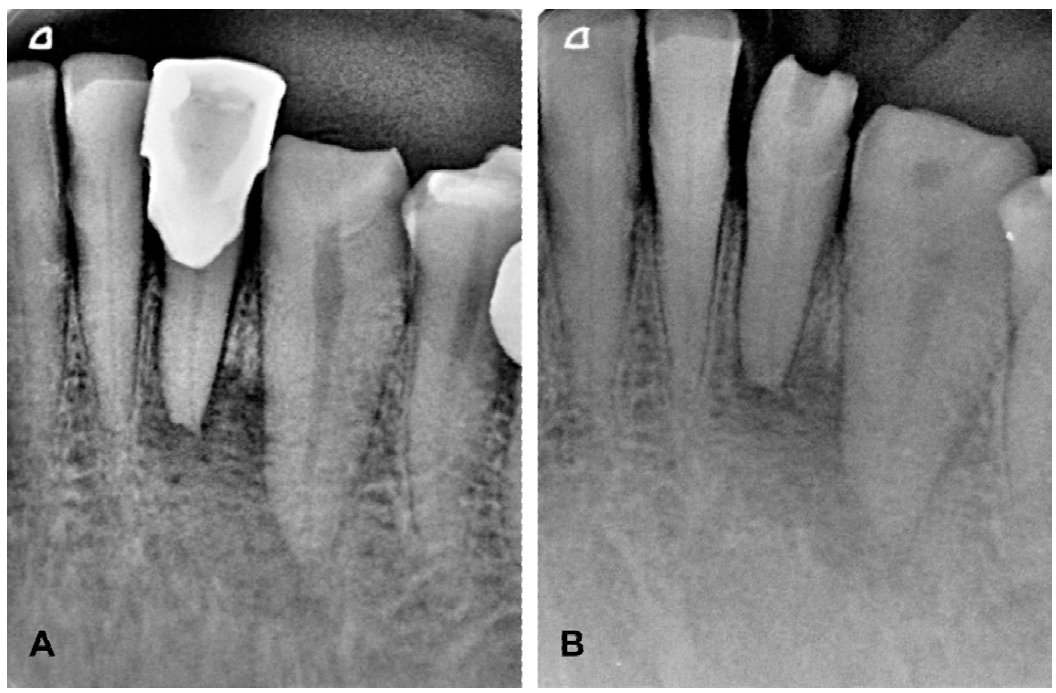

Se realizó la anamnesis de rutina con respecto a la sintomatología de las piezas 32 y 33. Refirió dolor a la percusión, de 7 de acuerdo a la Escala Visual Analógica (EVA). Se realizó prueba térmica al frío, aislando los dientes con dique de goma sin grapa, colocando vaselina, empapando una torunda de algodón con tetraflouretano (HYGENIC® Endo-Ice Spray refrigerante, COLTENE® Inc. Altstätten, Suiza), refiriendo sensibilidad 0 en EVA. Se realizó radiografía dentoalveolar con técnica de paralelismo (Figura 2. A), observándose una zona radiolúcida y reabsorción radicular en el diente 32 y desgaste incisal severo en el diente 33. Según sintomatología y signos, se diagnosticó el diente 32 con periodontitis apical crónica y el diente 33 con necrosis pulpar parcial aséptica. Igualmente se realizó una ortopantomografía para comprobar o descartar cualquier otra afección en la cavidad oral.

Figura 2 Radiografías dentoalveolares de los dientes 32 y 33. A. Radiografía preoperatoria de los dientes 32, con corona fenestrada, y 33. B. Radiografía postoperatoria, donde se colocó medicación intraconducto de Hidróxido de Calcio químicamente puro y ionómero de vidrio como obturación coronal provisional.